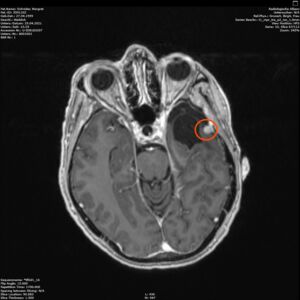

Am 03. November war mein Kontrollbesuch beim MRT. Leider ist ein kleiner Befund aufgetaucht. Schau das Video, dann kannst Du sehen.

Nun kann sich zeigen, ob die menschliche Medizin eine Lösung für mich hat. Möglichkeiten gibt es. Sogar mindestens eine, die der Neurochirurg als fein und elegant beschreibt. Gamma-Knife, eine Strahlentherapie. Klingt etwas nach Star Wars – man wird sehen, etwas abwarten ist auch drin.

Am 29.4.2021 war ich zum Kontroll-MRT drei Monate nach der hochmodernen Strahlentherapie, dem Gamma-Knife. Leider ist das Ergebnis: den Tumor hat diese Behandlung nicht beeindruckt, keine Änderungen zu erkennen. Der Arzt schlägt eine weitere Kontrolle in 6 Monaten vor. Ich finde es etwas schwer, dieses Ergebnis einzuordnen. Aber so ist es nunmal. Vielleicht ist es ja normal, und wird erst später gut (siehe Punkt 4).

Heute war ich im MRT im Bremen. Der Befund des auswertenden Arztes ist, dass er der Meinung ist, dass der Tumor etwas gewachsen ist. Ich habe mir die Bilder angesehen und versucht diese Aussage zu verstehen. Vermutlich ist sie richtig, aber das Wachstum ist nicht heftig nur vielleicht von 0,7 cm auf 0,8 cm. Aber Gamma-Knife hat es offensichtlich nicht entfernt.

Zu meinem Geburtstag am 27.4. habe ich sehr schöne Geschenke bekommen und kann mich auch über meinen bunten Garten freuen, im Herbst gab es ein Tulpen-Sonderangebot, dem konnte ich nicht wiederstehen! Und nun ist das Ergebnis zu sehen. Am 28. April war wieder mal MRT-Termin. Leider hat es an dem Tag eine Vertretung des auswertenden Arztes gegeben, die Ärztin war super freundlich aber hat keine ganz konkreten Aussagen machen können, aber sie hat mir 2 CDs gebrannt, ich konnte eine gleich bei den Neurochirurgischen Ambulanz abgeben und eine mit nach Hause nehmen. Mein Blick auf die Bilder hat eine nazu unveränderte Lage gezeigt.

Heute war der Termin beim Chirurgen, leider schon um 9:00 Uhr und natürlich wollte ich die knapp 20 km mit dem Rad zurück legen, Stephan wollte gerne mitkommen. Leider war die bereits abgegebenen CD nicht eingelesen worden und so musste erstmal die Datenverarbeitung arbeiten und wir warten, bis wir eine Auskunft bekommen konnten. Fazit: Der bestehende Tumor ist kaum gewachsen. Aber es hat sich leider ein 2. Fund ergeben, sehr klein aber deutlich sichtbar. Aber Maßnahmen sind erstmal nicht notwendig.